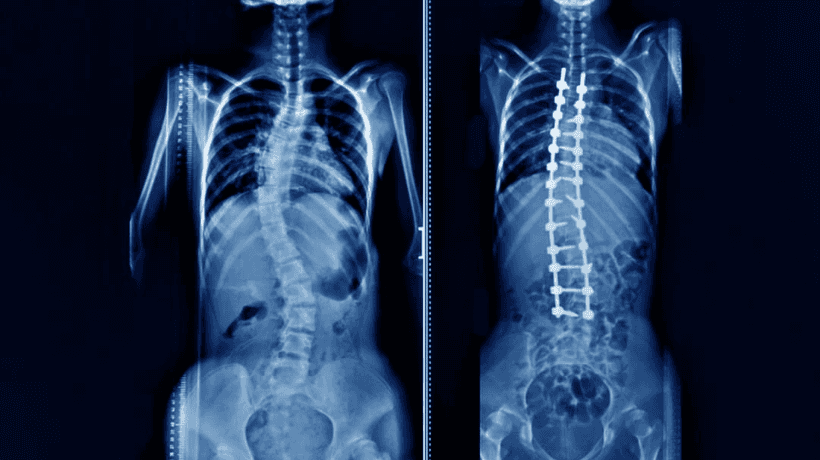

Healthtrip ቡድንስኮሊዎሲስ ከአከርካሪ አጥንት ጋር የተዛመደ ኩርባ ሲሆን ይህም በእብጠት እድገቱ ወቅት እና ከጉርምስና በፊት ነው. በዚህ ምክንያት ስኮሊዎሲስ መጥፎ ኩርባ ሊወስድ ይችላል። ሽባ መሆን, እና ጡንቻማ ዲስትሮፊ, ምክንያቱ የማይታወቅ. አብዛኛዎቹ ጉዳዮች ቀላል ናቸው, ጥቂት የሚታወቁ ምልክቶች. ልጆቹ እያደጉ ሲሄዱ ውስብስቦቹ ጎልተው ይታያሉ. አንዳንድ ጊዜ ለቀዶ ጥገና የሚያስፈልጉ መስፈርቶች አሉ, በሌላ ጊዜ ደግሞ ማሰሪያው እንደ ተአምር ይሠራል.

ስኮሊዎሲስ ቀዶ ጥገና

- የፊተኛው አቀራረብ የአከርካሪ አጥንት ዋና ዋና የተጎዱትን ክፍሎች ሸክም የሚጋራ ተጨማሪ የክፍል እንቅስቃሴን ይፈቅዳል የማገገሚያ ጊዜ ከ 4 ሳምንታት ያነሰ ነው

- ቀዶ ጥገናው የአከርካሪ አጥንቱን ማቆም አለበት

- ስኮሊዎሲስ በልብ እና በሳንባዎች ላይ ተጽዕኖ ሊያሳድር ይችላል።. ጉዳት የሚከሰተው የአከርካሪው ኩርባ 70 ዲግሪ በሚሆንበት ጊዜ ነው. የ 100 ዲግሪዎች ኩርባ በልብ እና ሳንባዎች አቀማመጥ ላይ ከባድ ጉዳት ያስከትላል.

- ቀዶ ጥገና ሌላ የወደፊት የአከርካሪ ህመም እና የአርትራይተስ ጉዳቶችን ይከላከላል.